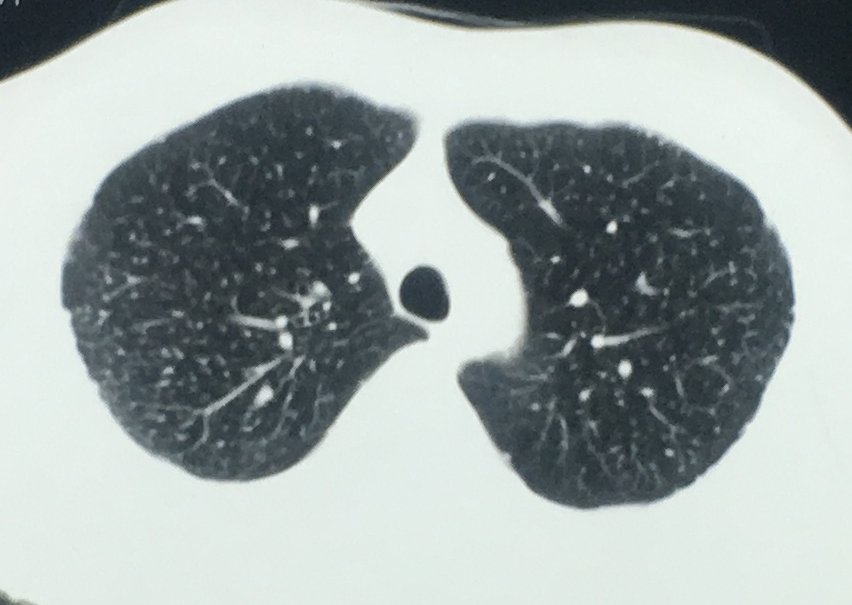

2. 血行播散性肺结核:急性血行播散性肺结核表现为两肺均匀分布的大小、密度一致的粟粒阴影;亚急性或慢性血行播散性肺结核的弥漫病灶,多分布于两肺的上中部,大小不一,密度不等,可有融合。需与电焊工尘肺、肺转移瘤等其他疾病鉴别。

*血行播散性肺结核:均匀分布的大小、密度一致的粟粒结节